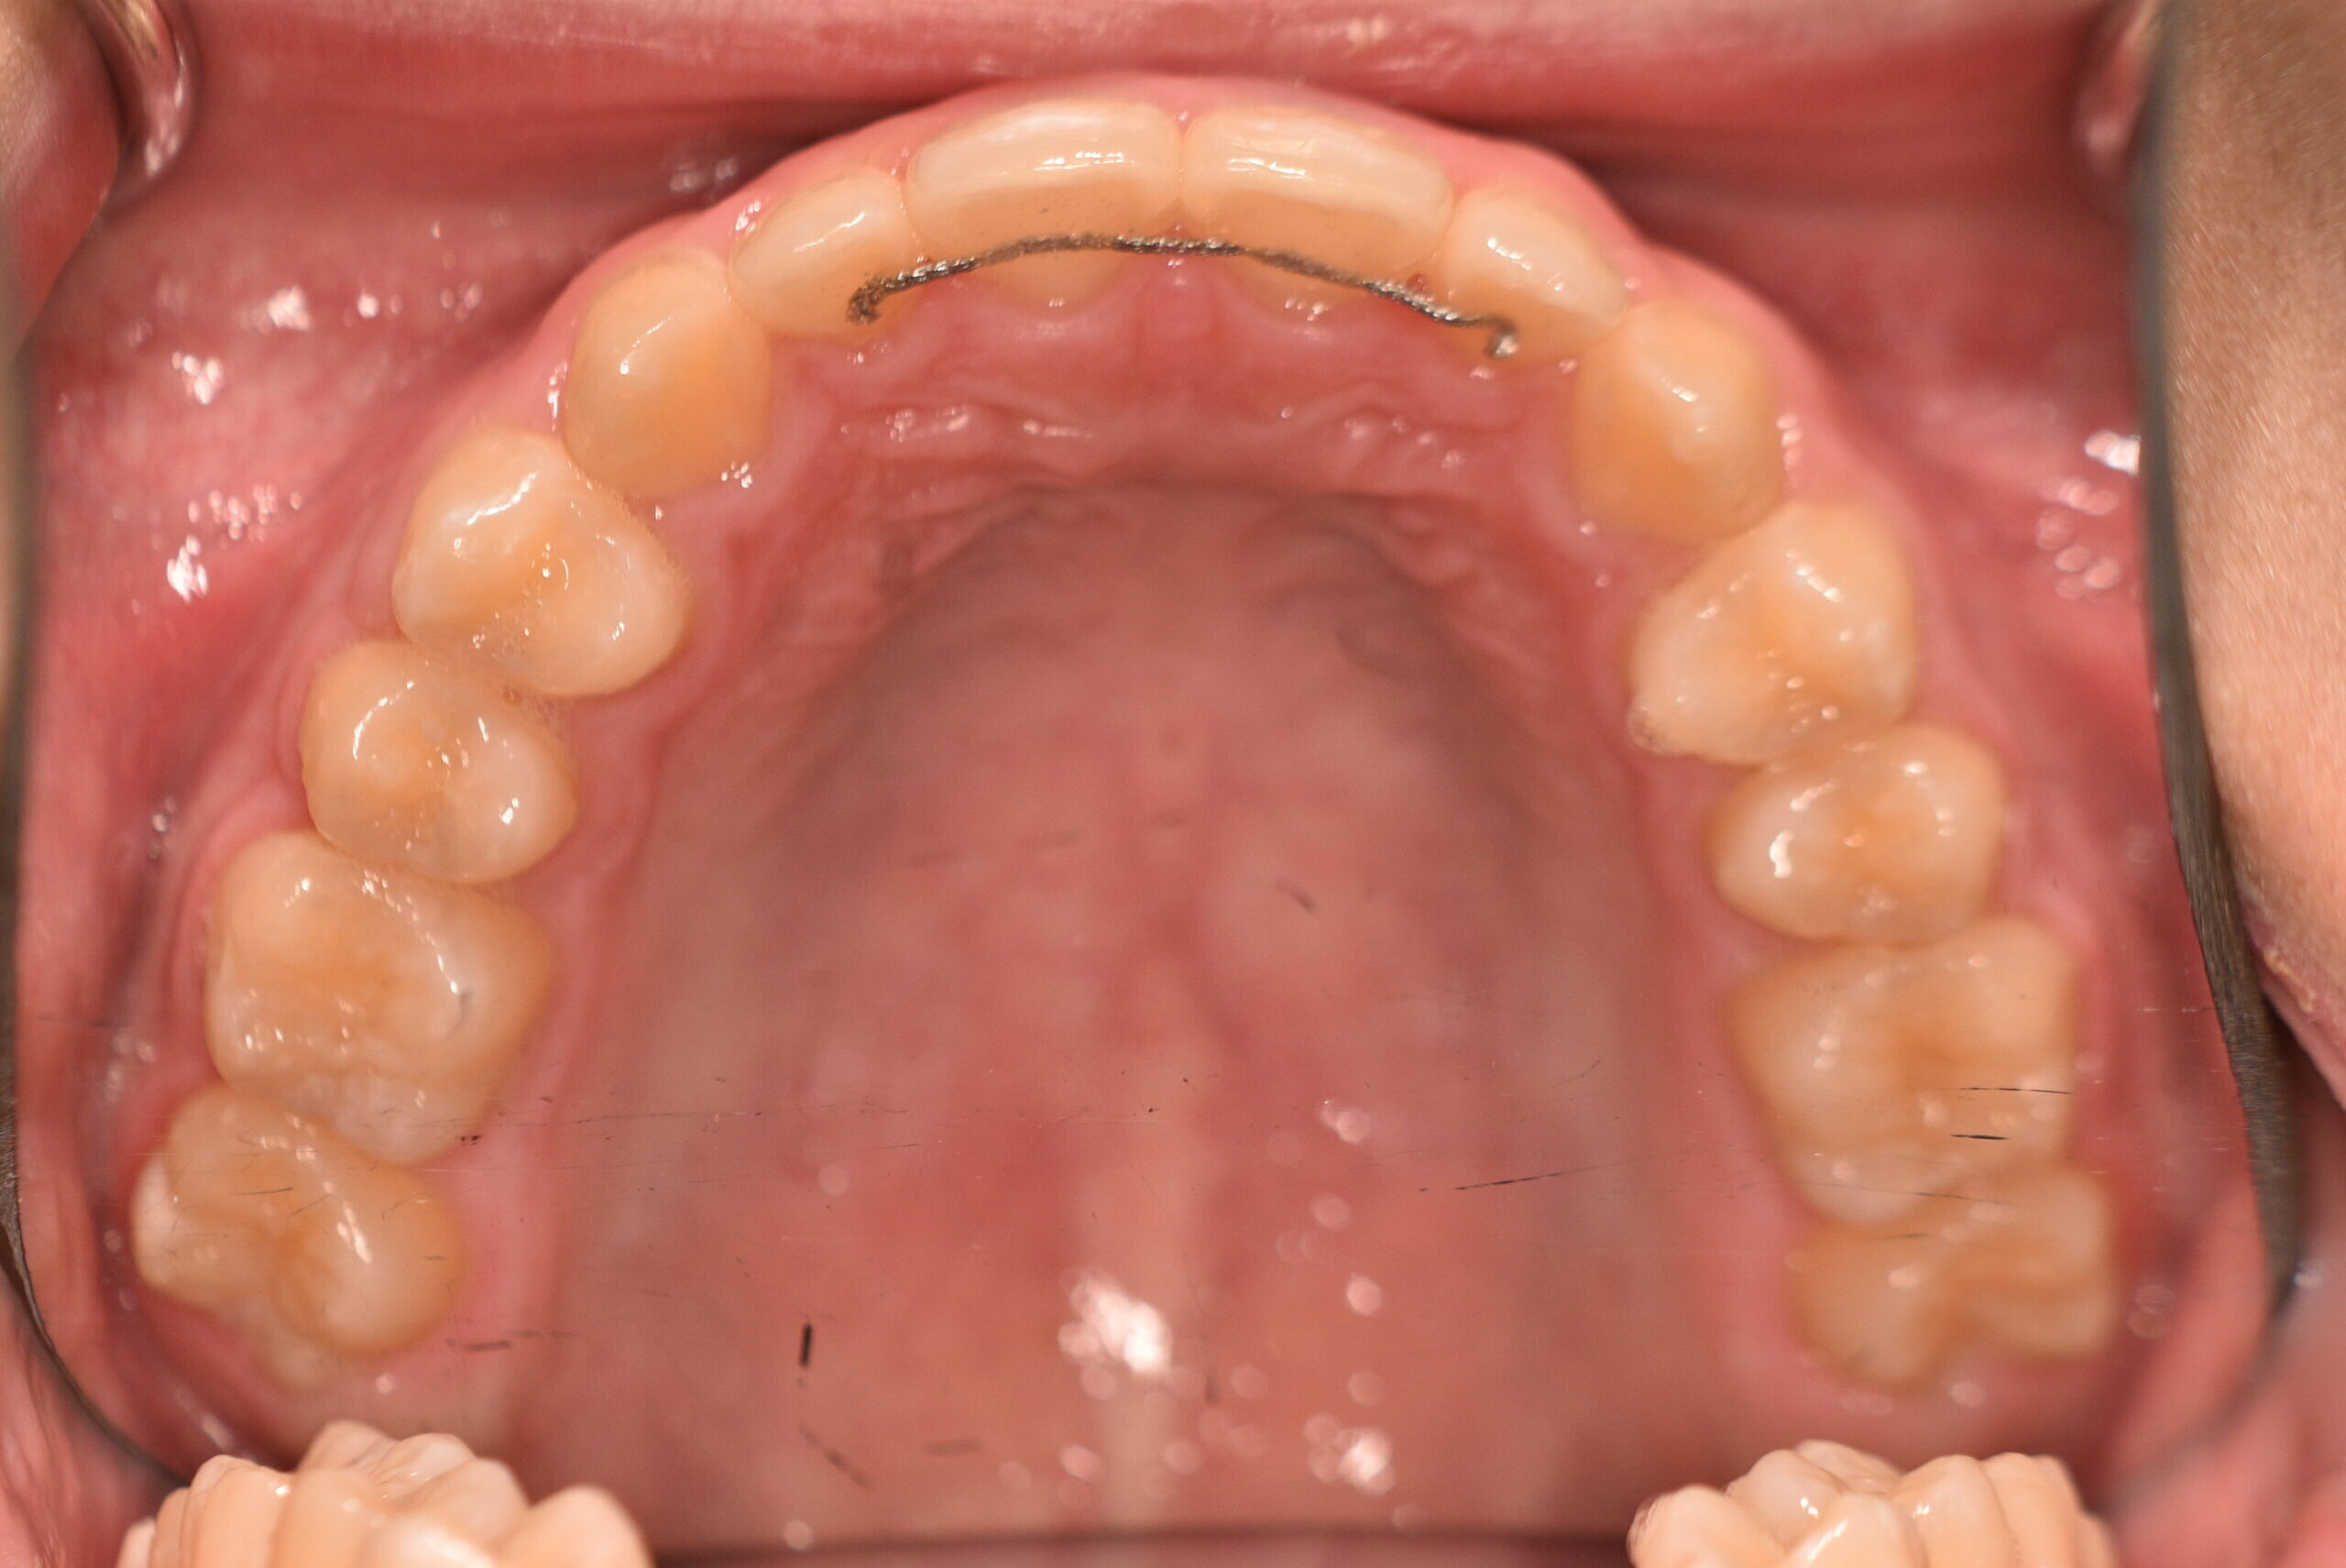

| 治療内容の詳細 | 初診時6歳の男性で、受け口を気にされ来院されました。 検査の結果、反対咬合を伴うアングルⅢ級不正咬合と診断しました。 治療としては、初期段階の治療として、機能的矯正装置で鼻呼吸の獲得と舌の位置や口唇の閉鎖といった筋機能習癖の改善を行い、上顎前方牽引装置を使用し上顎骨の前方方向への発育を誘導し、反対咬合の改善を行いました。 永久歯列に交換後、非抜歯の上、セルフライゲーションブラケット装置(デーモンシステム)で歯の配列と咬合関係の改善を行いました。 治療期間は、7年3ヶ月でした。 |